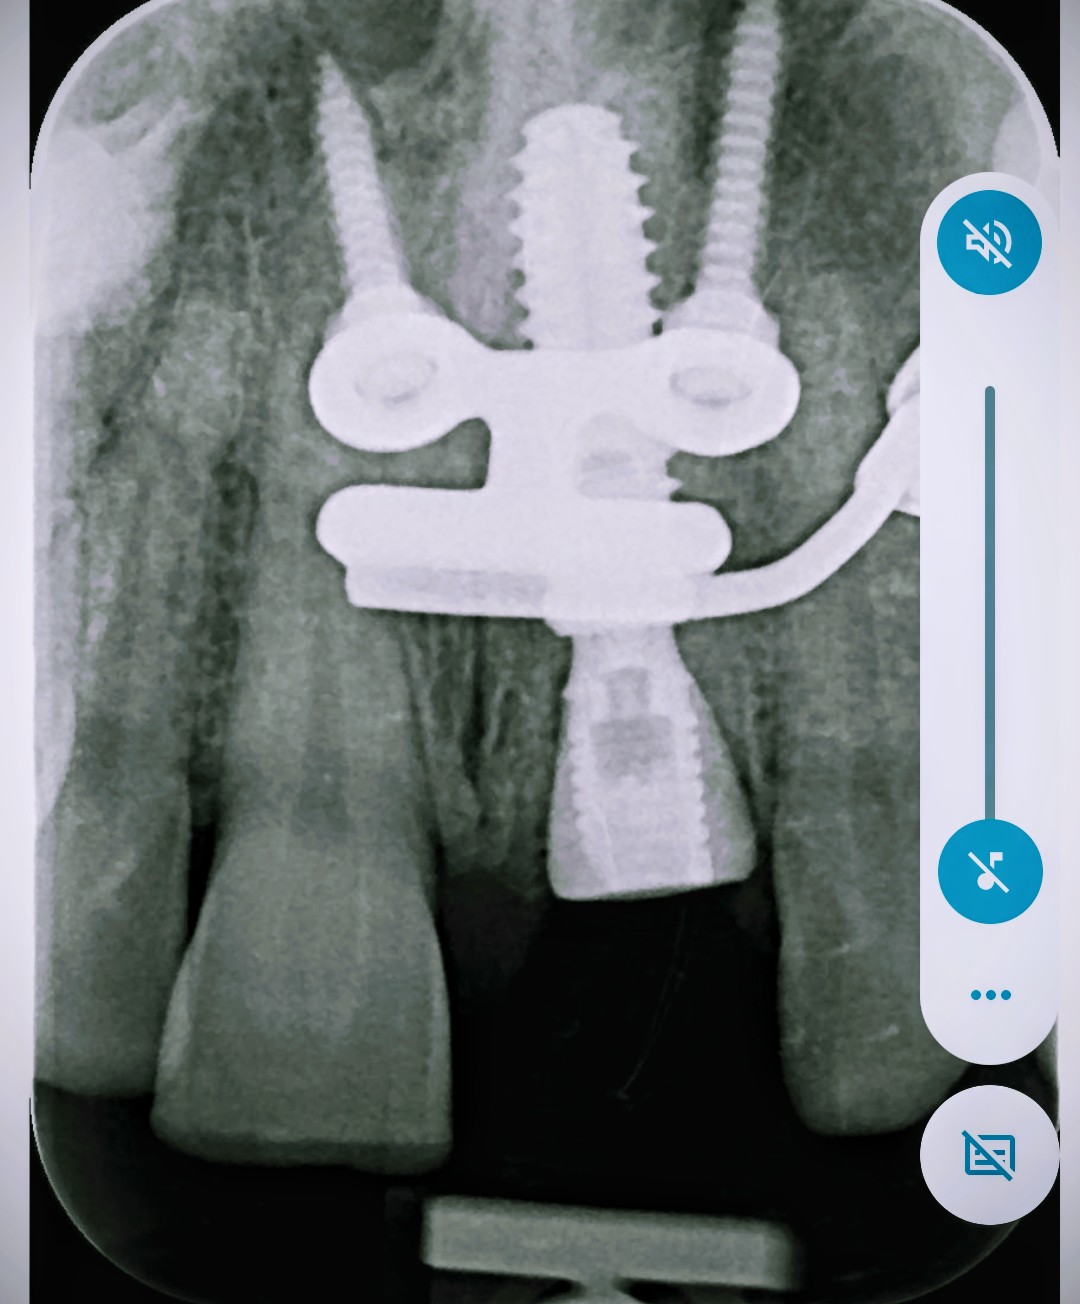

Implant placed too deep, anterior

Today i inserted imediat postextractional a Bredent copaSky 4x14, in socket 21, after a Root fracture in the middle.third.

The torque was poor around 25 Ncm. I tried to engaged more apically but stilul no high torque, stilll 20-25 Ncm.

I made buccal gbr with bone graft, prf, and CTG. The implant îs 5 mm bucal , drom the gingival margin, and 3 mm from.the buccal plate. I made a customed healing abutment.

im confused. how you know your implant is 3mm from the buccal plate. the sagittal view you provided is a planned implant position not the actual CT scan of post implant placement. from your PA. the implant seems more than 5mm from the gingival margin. more like 8mm.

Also what’s that screw and plate? is that the surgical guide? couldn’t you use just a tooth supported surgical guide. Kinda over kill and more trauma for single tooth site.